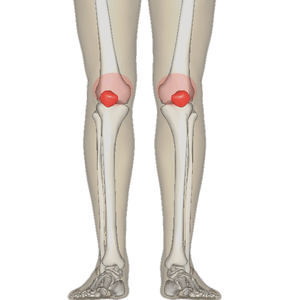

| Diagram of the bones of the lower extremity. Rough distribution of areas affected by PFPS highlighted in red: patella and distal femur. | |